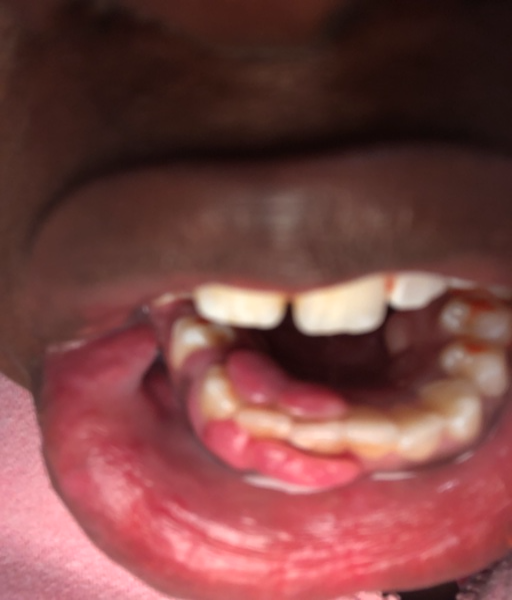

So for 4 weeks I've had this gone rouge canker sore. I'm getting it surgically removed in 2 months. It's so noticeable although it's in the inside of my bottom lip. I also wear bottom retainers and that makes the pain 2x worse. What can I do to reduce it or completely remove it. I've tried staying away from sugary or acidic food but that doesn't help, please help me. I'm scared it'll bust and leave a forever mark on my my mouth.

Answer: Aphthous Ulcer

Recurrent aphthous stomatitis is a common ulcerative inflammatory condition of the mouth. It is referred to as RAS. The lesions appear as small, painful, round or ovoid ulcers and usually start in adolescence. Recurrent Aphthous stomatitis is diagnosed from history as well as clinical features, with a positive family history. Not all recurring ulcers are RAS, so it must be determined if there is an underlying systemic disorder. Some common causes of RAS include psychological stress, nutritional deficiency, dietary allergies, trauma and genetic susceptibility. If you are under high stress, trauma or not eating properly, try treating that condition as well. Ulcers with similar characteristics that rarely resolve spontaneously with age are usually indicative of a systemic condition such as an auto-immune disorder. Once diagnosed with RAS based on clinical features and history, topical corticosteriods can be prescribed and remain the treatment of choice. Prior to surgery, a corticosteroid may be an option.